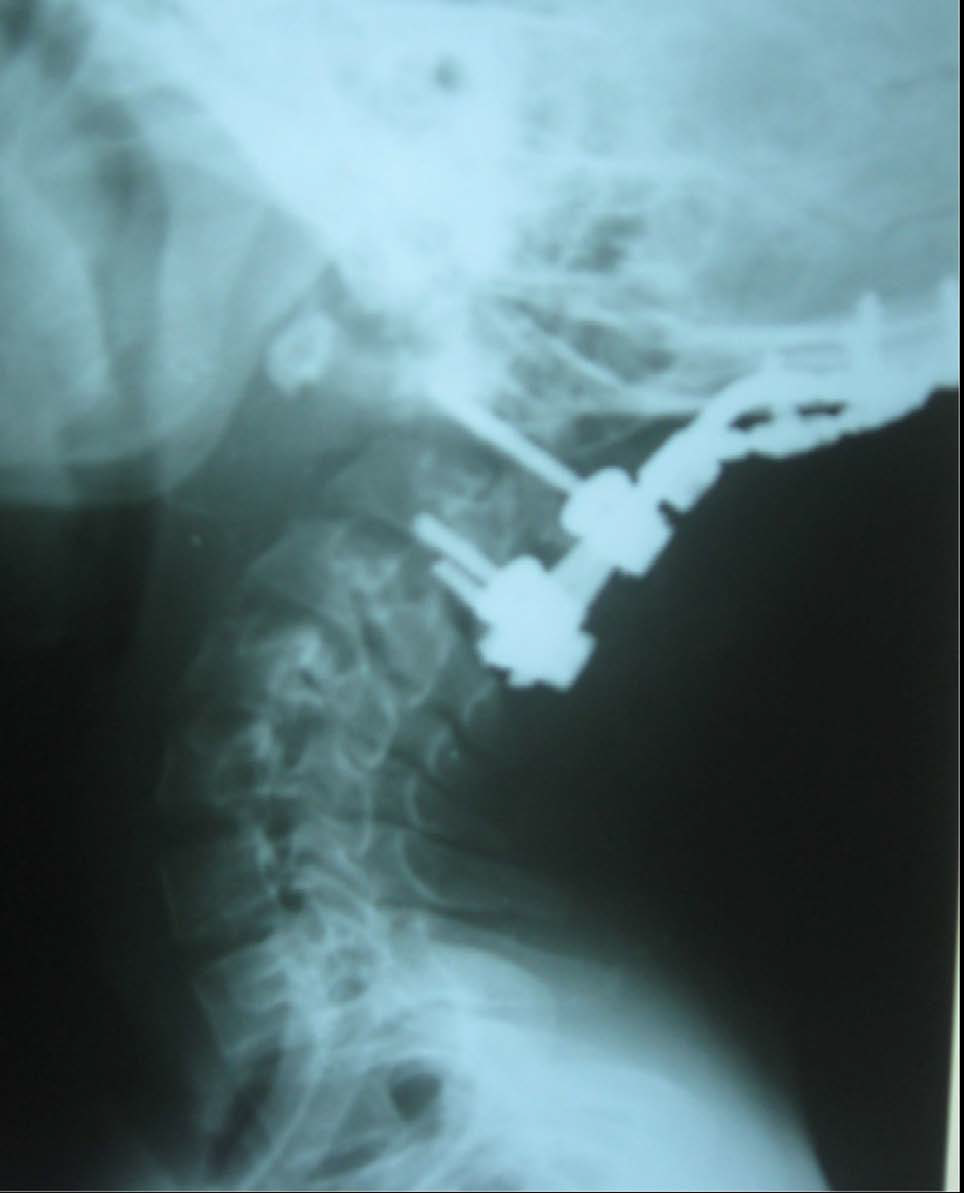

Figure 1: Type II odontoid fracture, Obar, treated by posterior approach. Cervical profile radiograph showing the screw-rod technique interconnecting polyaxial screws at C1 and C2 (Harms’s technique); and screws at occiput with rods.

figure 1